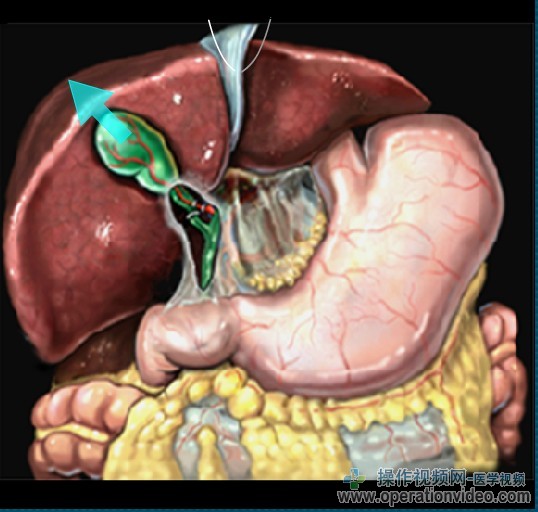

腹腔镜胆总管探查:TRANSCYSTIC方法

一旦达到足够的胆囊管直径,结石可通过以下几种方式是在X线透视或胆道镜指导,或盲目程序中删除。最终的目标是彻底清除胆道结石,避免胆管损伤。他们似乎从胆囊管进入腹腔或逃逸到小囊的腹膜,用纱布垫或内窥镜提取包可以放在后面的肝十二指肠韧带和捕捉结石的胆囊颈部以下的预防结石。

内镜引导下取石,包括以下步骤:

-胆道镜的引进和可视化的石头(S);

-引进的Dormia篮通过操作通道(或胆道镜一起)进入CBD。石头检索,由Dormia购物篮针对所述内窥镜的前端牢固地保持

胆道镜与Dormia篮子在持续的视图被撤回。

它是强制性的,以确认已完全清除,CBD。这可能与胆道镜,胆道造影或超声检查。

“生物多样性公约”的探讨乳头。以上,内镜下胆管和“生物多样性公约”结探索是困难的。在怀疑结石位于近侧的情况下,有,胆管造影应进行。

通过胆囊管当直接提取的石头的大小是不可能的,因为,它可能有必要使沿胆囊管的纵向切口的突起的上在石头上。石头然后可以提取使用无创伤抓取(见视频)。